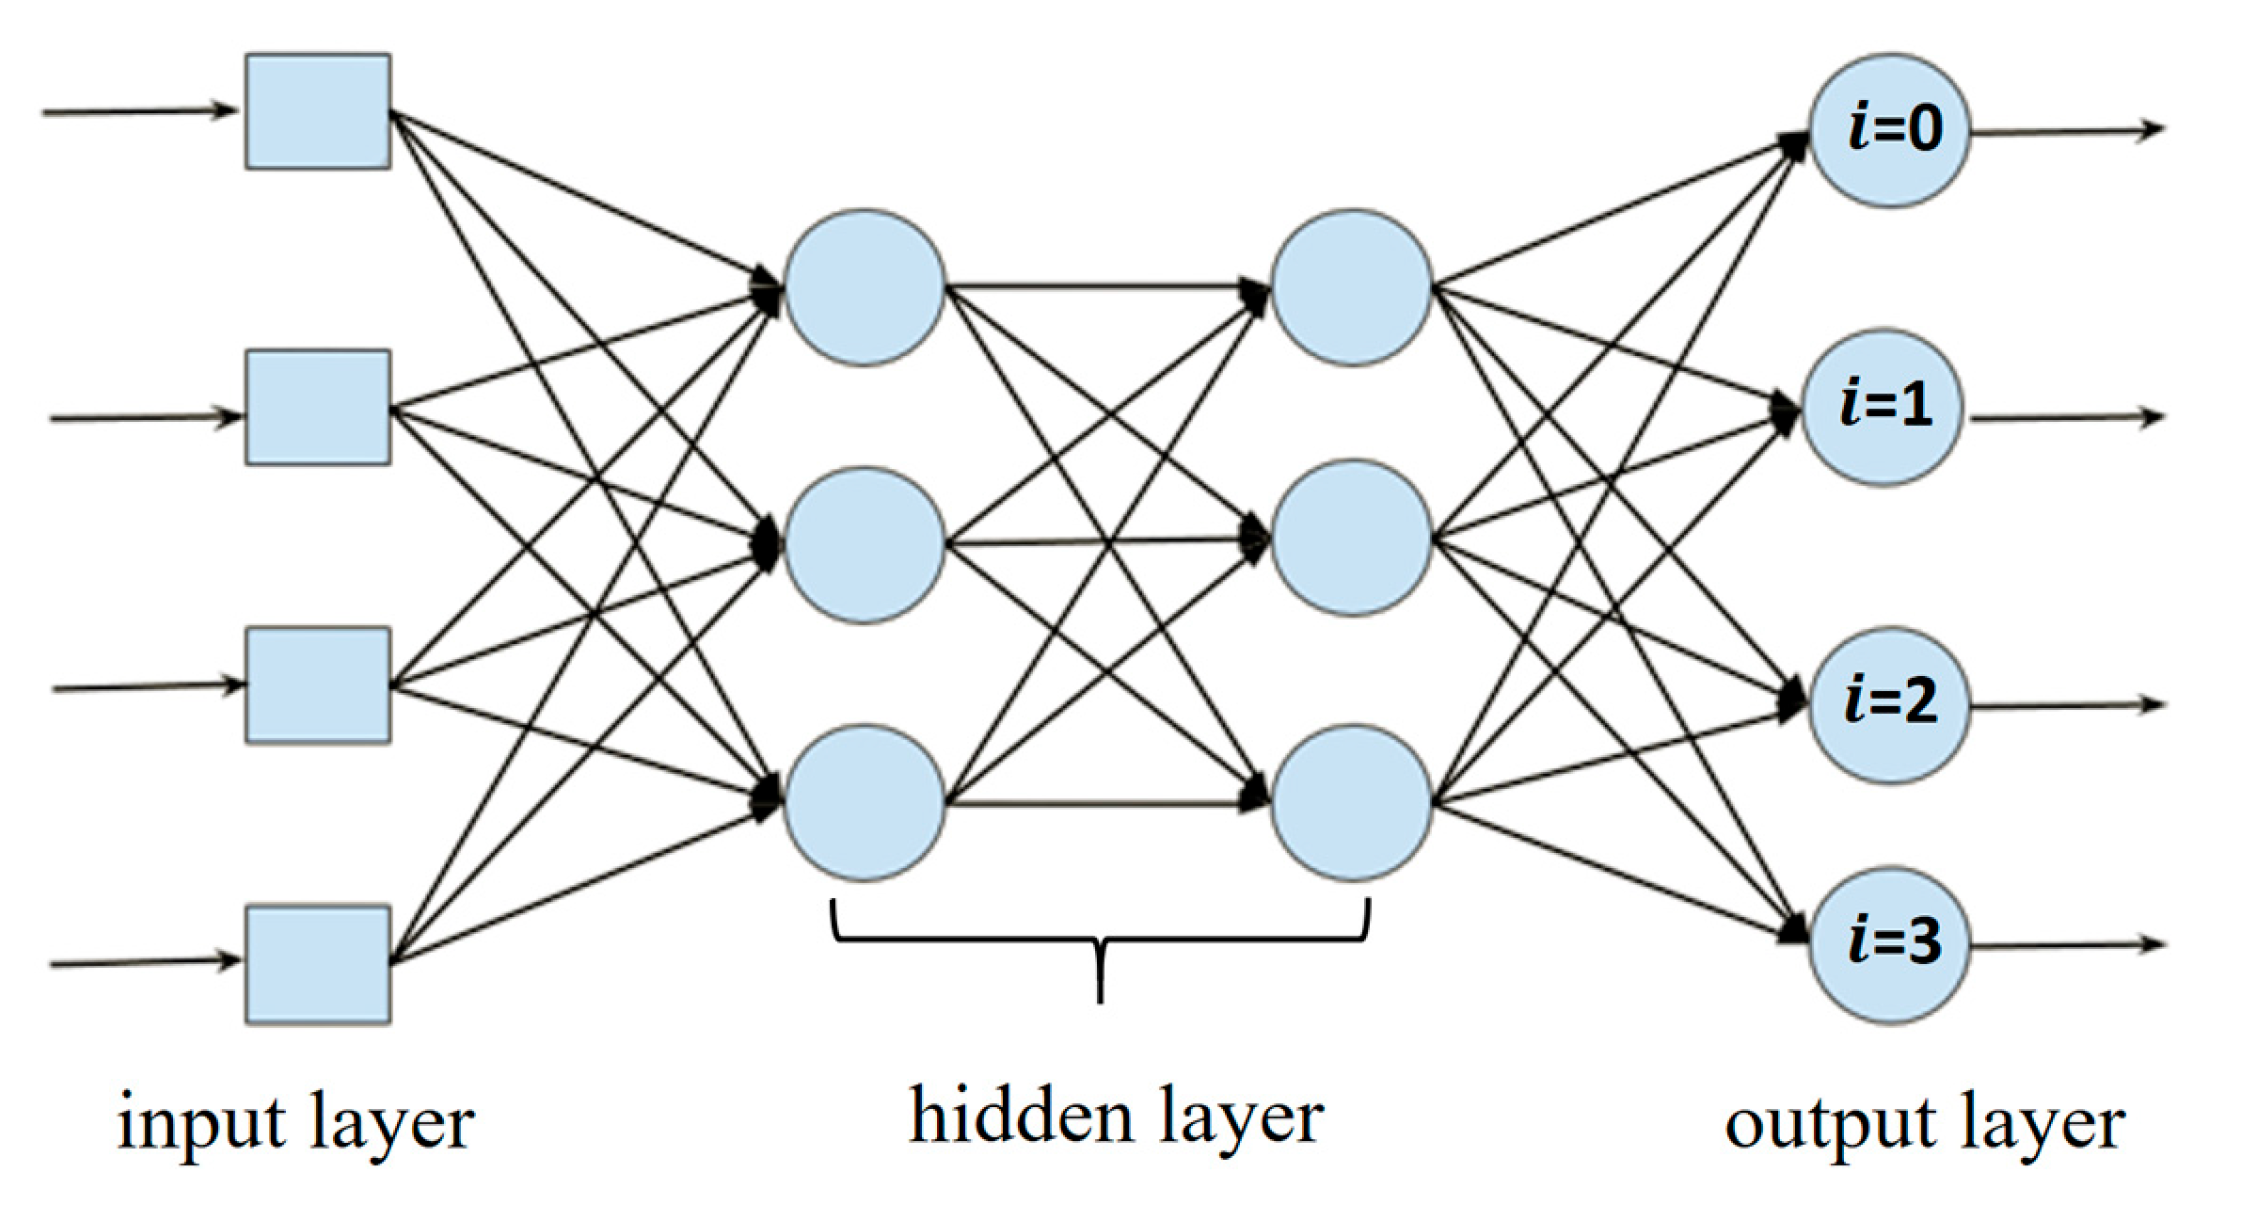

2. Related Work

3.1. Research Framework